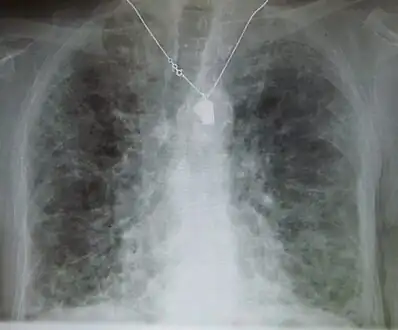

Side effects of amiodarone include various pulmonary effects.[22] The most serious reaction that is due to amiodarone is interstitial lung disease. Risk factors include high cumulative dose, more than 400 milligrams per day, duration over two months, increased age, and preexisting pulmonary disease. Some individuals were noted to develop pulmonary fibrosis after a week of treatment, while others did not develop it after years of continuous use. Common practice is to avoid the agent if possible in individuals with decreased lung function.

The most specific test of pulmonary toxicity due to amiodarone is a dramatically decreased DLCO noted on pulmonary function testing.